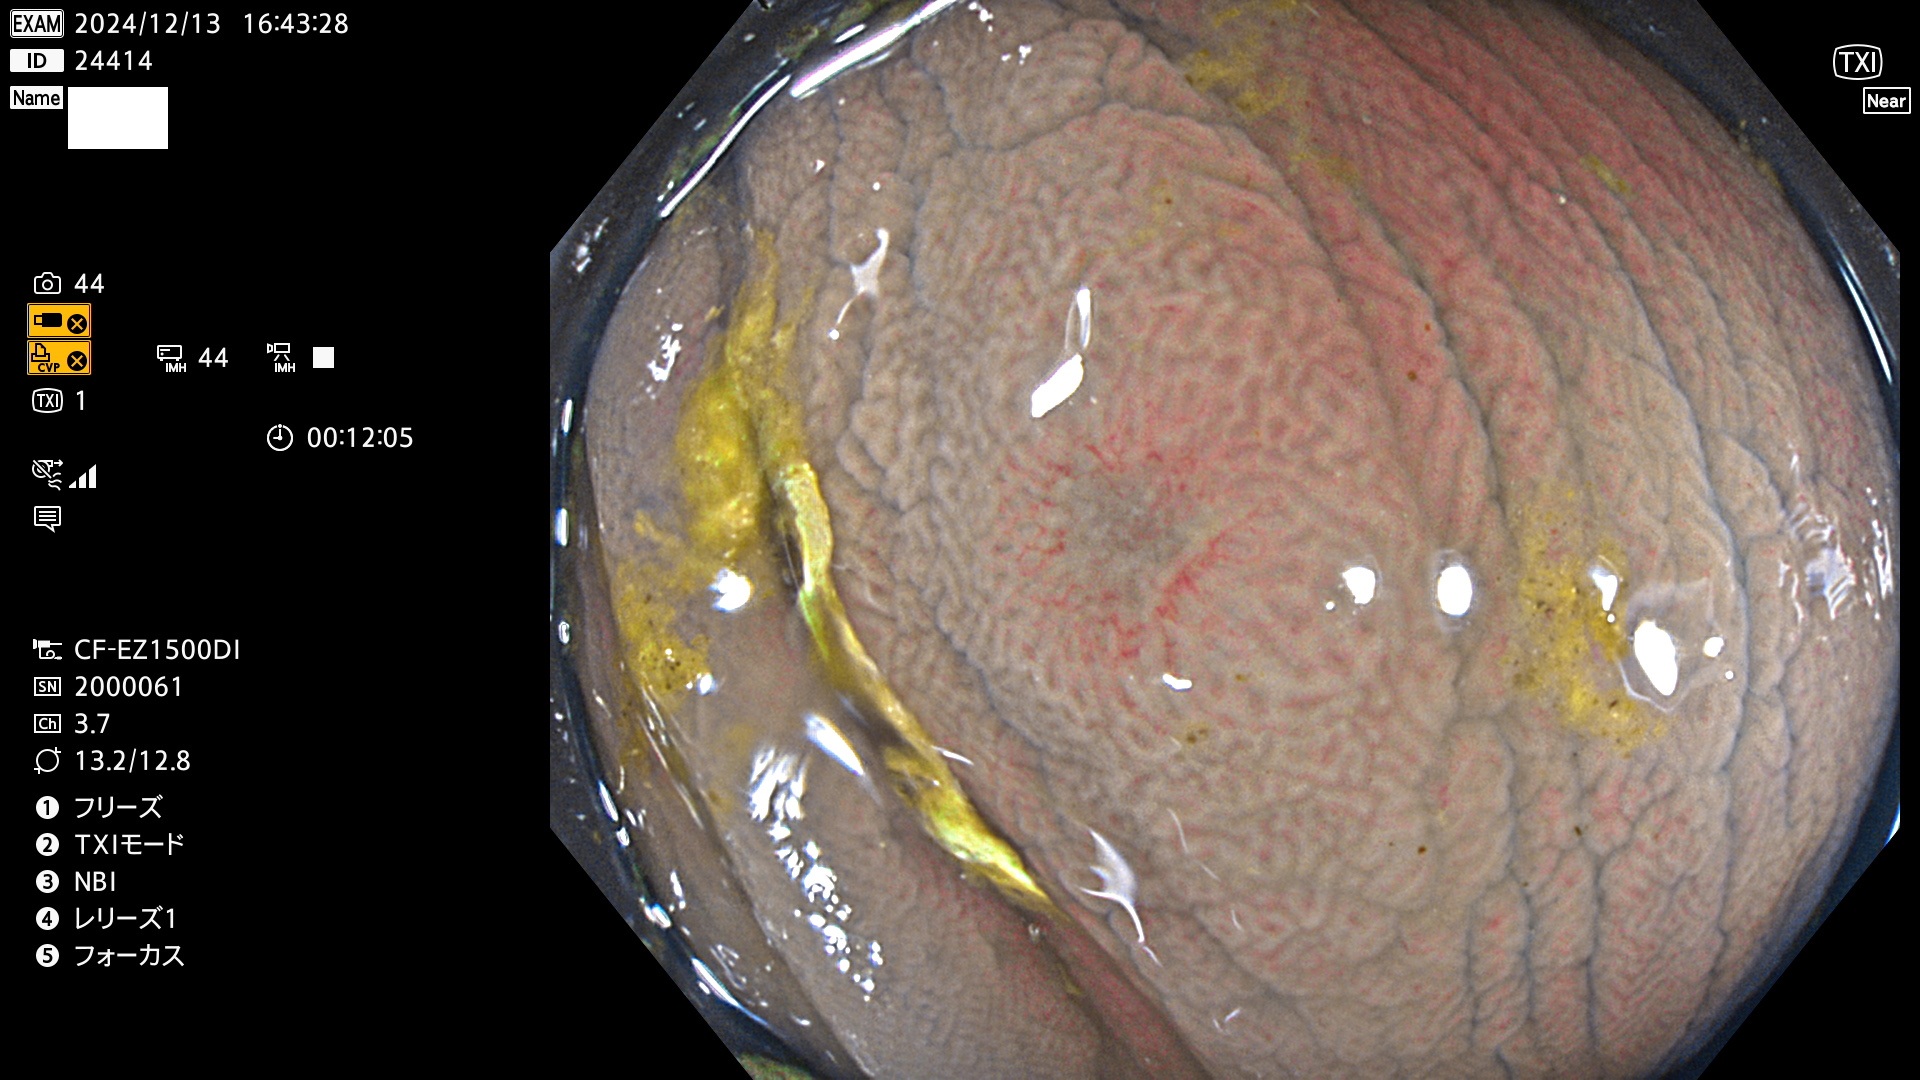

今週のUb、Uc型腺腫

完全に平坦な物をUb、陥凹している物をUcと呼びます。最も発見が難しく危険な病変です。

毎週の検査(木・金・土・日)に発見されたUb、Uc型・腺腫を、その週の日曜の夜にUPし1週間、提示します。

抽出の対象期間 2024年12月12日〜12月16日の5日間(60件の検査)13件 (13/60=21%)